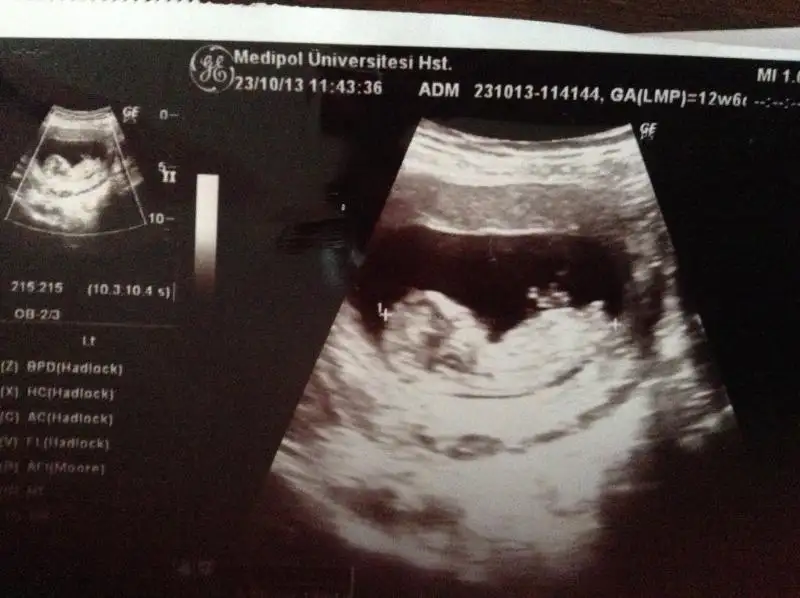

Kızlar selamlar ben de size bir video ve ultrason görüntülerimizi ekliycem. biz anlayamadık, siz anlarsanız lütfen yorumlayın. Bekliyorum, sevgiler...

Videoyla daha iyi anlayabileceğinizi düşünüyorum:

12+0 hafta - YouTube

Eki Görüntüle 867635 Eki Görüntüle 867636 Eki Görüntüle 867638

cinsiyeti ne olabilir nubu göremedim ben

Cok baktim ama ultrasonun goruntu kalitesi dusuk canim ya gorunmuyor hic doktor bi tahminde bulunmadimi